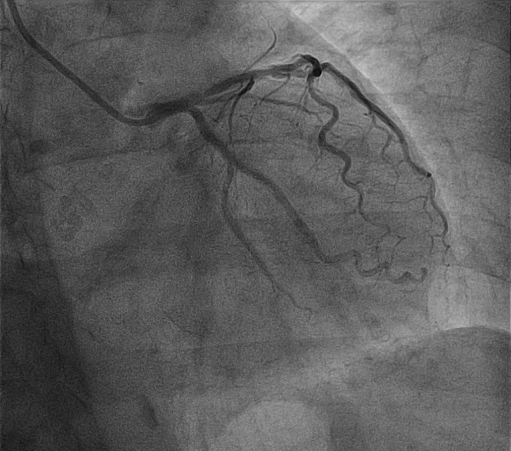

植入支架

经过充分的冲击波球囊预处理后,因钙化环得到松解,血管顺应性提升,病变处顺利植入支架2枚。术后造影提示支架贴壁良好,扩张满意,无残余狭窄。

成功置入支架,支架贴壁良好,扩张满意,无残余狭窄